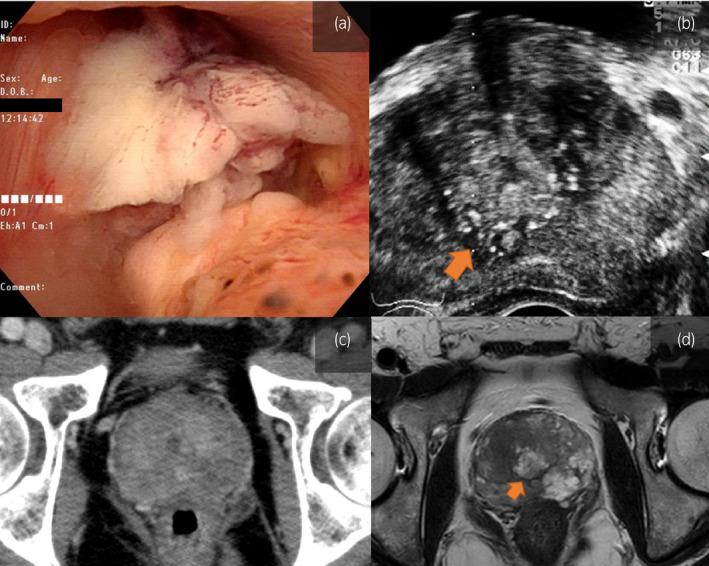

Mucinous urethral adenocarcinoma is a rare and progressive cancer of the prostatic urethra. Reports on palliative systemic treatment for mucinous urethral adenocarcinoma are few. We present a case of coexisting mucinous urethral and prostate adenocarcinomas managed with systemic treatment.

CASE PRESENTATION

A 66-year-old man presented with gross hematuria and urinary retention. Prostate-specific antigen level was elevated, at 99 ng/mL, and prostate biopsy revealed moderately to poorly differentiated adenocarcinoma. Hormone therapy and standard chemotherapy for prostate adenocarcinoma were ineffective. Prostate re-biopsy revealed coexisting mucinous urethral and prostate adenocarcinomas. Gemcitabine + cisplatin chemotherapy and folinic acid + 5-fluorouracil + irinotecan chemotherapy temporarily suppressed the cancer, but 14 months after presentation, he developed liver metastasis and died. Autopsy revealed metastasis of both mucinous urethral adenocarcinoma and carcinosarcoma.

CONCLUSION

Mucinous urethral adenocarcinoma is difficult to diagnose in coexistence with prostate adenocarcinoma. This was an extremely rare case showing chemoresistance due to epithelial-mesenchymal transition.